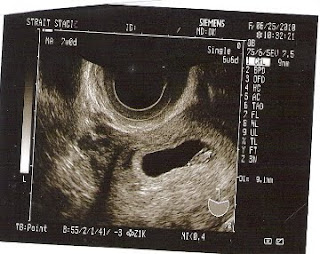

It's true! Here's number 2! Due February 11, 2011!

The doctor said it was safe to announce! We announced it officially at Hayden's birthday party yesterday with the little birdie shirt! You should have seen some of those shocked faces!